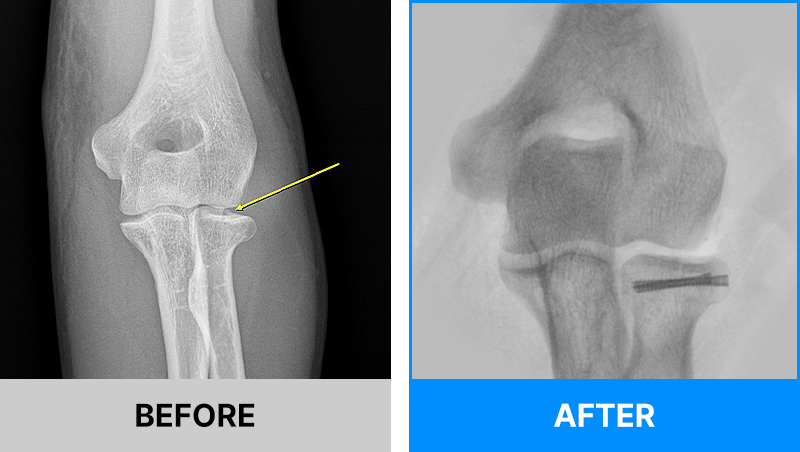

왜 당일 입퇴원 수술일까요?

오래 입원할 필요가 없기 때문입니다.

서울거탑정형외과에서는 전신마취, 척추마취가 아닌

국소부분마취(신경차단) 및 수면 마취를 통해 수술을 시행합니다.

수술 가능 여부 확인은 대표원장과의 진료가 필요합니다.